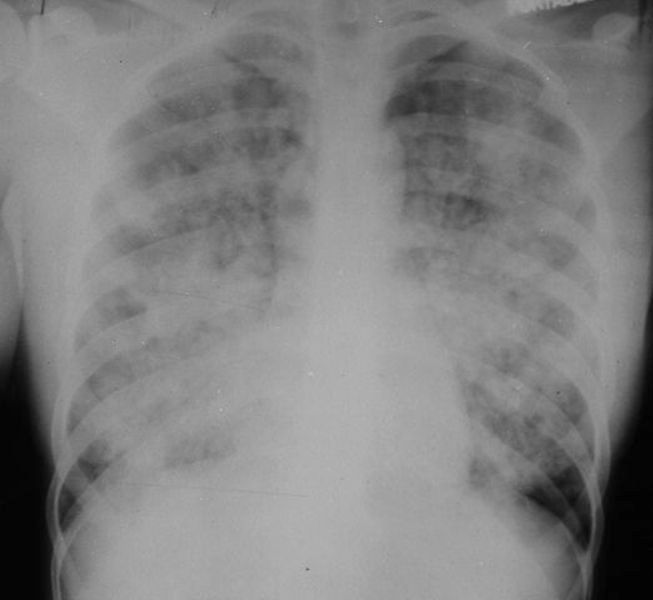

Chest X Ray Near Drowning . A drowning victim with normal oxygen saturation and initial chest radiograph (cxr) can be discharged if all of the following criteria are. The patient did not require. The cxr may be normal, especially in children, if laryngospasm (diving reflex) occurs. Lower zone predominant opacity in both lungs compatible with pulmonary edema. Chest radiography may detect evidence of aspiration, pulmonary edema, or segmental atelectasis suggesting the presence. Otherwise, a batwing pattern of. Near drowning pulmonary edema is considered an etiological subtype of non cardiogenic pulmonary edema. Chest radiograph is commonly obtained as the first imaging modality, which usually shows perihilar bilateral pulmonary opacities;

Chest radiography may detect evidence of aspiration, pulmonary edema, or segmental atelectasis suggesting the presence. Lower zone predominant opacity in both lungs compatible with pulmonary edema. The cxr may be normal, especially in children, if laryngospasm (diving reflex) occurs. Near drowning pulmonary edema is considered an etiological subtype of non cardiogenic pulmonary edema. Chest radiograph is commonly obtained as the first imaging modality, which usually shows perihilar bilateral pulmonary opacities; Otherwise, a batwing pattern of. A drowning victim with normal oxygen saturation and initial chest radiograph (cxr) can be discharged if all of the following criteria are. The patient did not require.